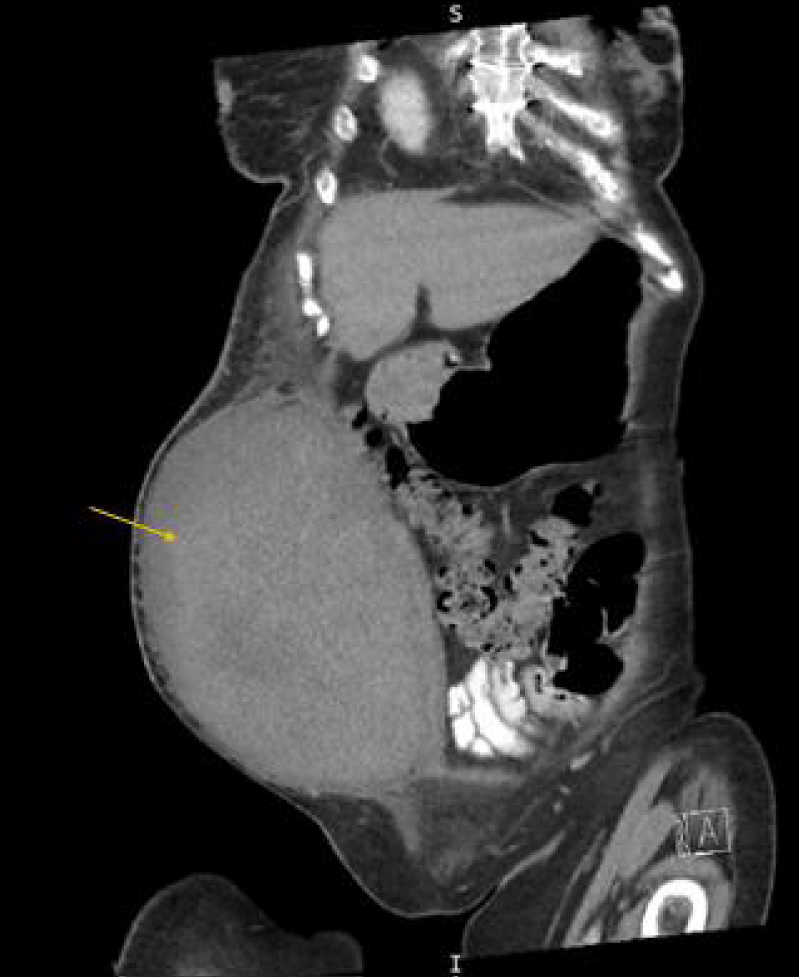

A 65-year-old woman with a history of coronary artery bypass grafting for severe coronary artery disease, mechanical mitral valve replacement on warfarin, persistent atrial fibrillation, and heart failure with reduced ejection fraction, presented with a two-day history of increased urination, fever, and bilateral flank pain. She was admitted for urosepsis and treated with intravenous fluids, vancomycin, and cefepime. Vancomycin was discontinued after blood cultures grew no bacteria at 48 hours and cefepime was continued for a total 5-day course. On day two of admission, her high sensitivity troponin increased from 24 ng/L to 1509 ng/L with EKG changes significant for atrial fibrillation with rapid ventricular response with a previously known left bundle branch block. There were no ST elevations or T wave inversions. Given her history of coronary artery disease and high suspicion of acute coronary syndrome, warfarin was transitioned to heparin, and she underwent cardiac catheterization via a right femoral access under ultrasound guidance. The Heparin drip was discontinued immediately before patient transportation for the catheterization. Right radial access was initially attempted but was unsuccessful due to radial artery vasospasm. Angiography showed no obstructive Coronary Artery Disease (CAD) and normal right heart pressure. Post-catheterization, the femoral access site was dressed with gauze and Tegaderm. Given the lack of CAD, troponin elevation was attributed to demand ischemia in the setting of sepsis. Four days post-catheterization, she developed new right lower quadrant pain and hypotension. Later the same day, the on-call team was notified that the hematoma in the right lower quadrant noted on ultrasound was rapidly expanding. Upon confirmation, the heparin was immediately discontinued, and the patient was upgraded to the medical intensive care unit. Initial computed tomography of the abdomen and pelvis (CTAP) was significant for a large right rectus sheath hematoma measuring 17 x 10 x 17 cm with concern for active extravasation from the right inferior epigastric artery. Subsequently, a right iliofemoral angiogram was performed for further characterization of the bleeding source and demonstrated a right Common Femoral Artery (CFA) hemorrhage into a PSA, not an inferior epigastric artery hemorrhage (Figure 1). The patient received Ultrasound-Guided Thrombin Injection (UGTI) with 300 units of thrombin injected into the right CFA PSA sac and closer to the neck with successful thrombosis and no further color flow within the PSA on repeat imaging. Heparin was re-started on day three, post-hematoma onset, after an in-depth risk-benefit discussion with the family. Bridge to warfarin was started on day ten post-hematoma onset after ensuring hematoma stabilization, hemoglobin stability, and no signs of skin ischemia or necrosis. 19 days after initial hematoma onset, a CTAP demonstrated the rectus sheath hematoma measuring 11.4 x 18.5 x 22.2 cm (Figure 2). The patient was discharged to an acute inpatient rehab facility and was later discharged from rehab after 14 days. Two months after the initial hematoma onset, an outpatient monitoring ultrasound was performed and showed a well-circumscribed heterogeneously hypoechoic structure measuring 15.5 x 14.0 x 10.5 cm. The patient had no further occurrences of bleeding

Download Image

Figure 2: Computed tomography of the abdomen and pelvis with contrast showing coronal view of the rectus sheath hematoma measuring approximately 11.4 x 18.5 x 22.2 cm 19 days post-onset.